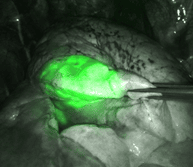

Mini-sonde endobronchique

De quoi s’agit-il ?

Cette technique nécessite un fibroscope bronchique, c’est-à-dire une caméra miniaturisée permettant d’explorer le poumon et les bronches de l’intérieur, par les voies naturelles.

La minisonde est une sonde de 2 mm qui s’insère dans le fibroscope permettant compte tenu de sa petite taille d’ aller plus loin dans les bronches de petit calibre. Cette minisonde est elle-même équipée d’une sonde d’échographie, miniaturisée à l’extrême, permettant d’examiner le poumon de l’intérieur.

A quoi ça sert ?

Ainsi des cancers à des stades plus précoces qu’auparavant peuvent être repérés et opérés.